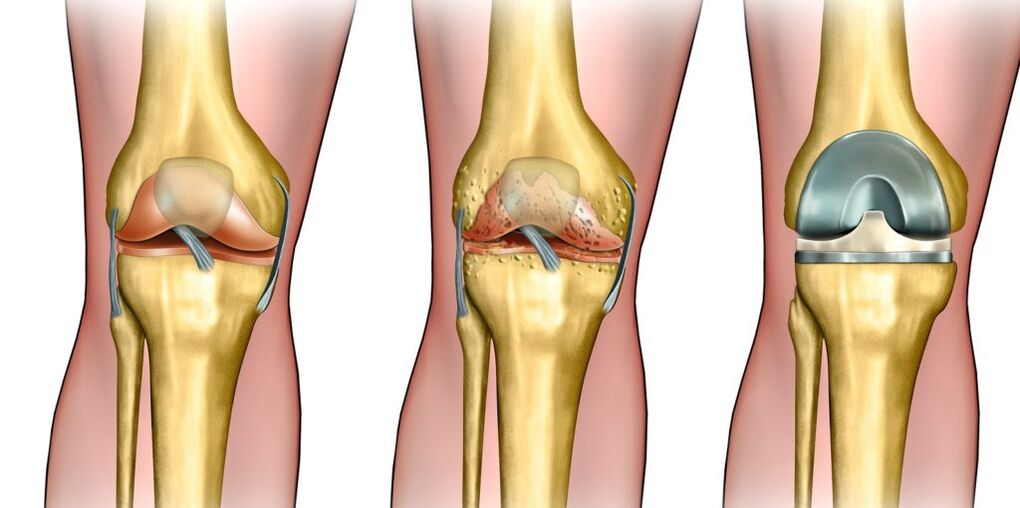

L'arthrose de l'articulation du genou (gonartrose) est une pathologie dégénérative de l'articulation, dans laquelle la destruction du cartilage se produit, les dommages aux muscles et aux ligaments et sur la déformation des os.

Avec le développement de la maladie, le cartilage commence à devenir plus mince en raison de fortes charges ou du manque de nutriments. Cela provoque le frottement des os à l'articulation du genou.

L'érosion sur le tissu osseux est formée comme une réaction protectrice du corps: la formation de croissances à ce sujet commence. Tous ces facteurs conduisent à la déformation de l'articulation du genou et de sa mobilité limitée.

L'un des plus efficaces: l'endoprothétique de l'articulation du genou, c'est-à-dire en remplaçant les surfaces de frottement de l'articulation artificielle.